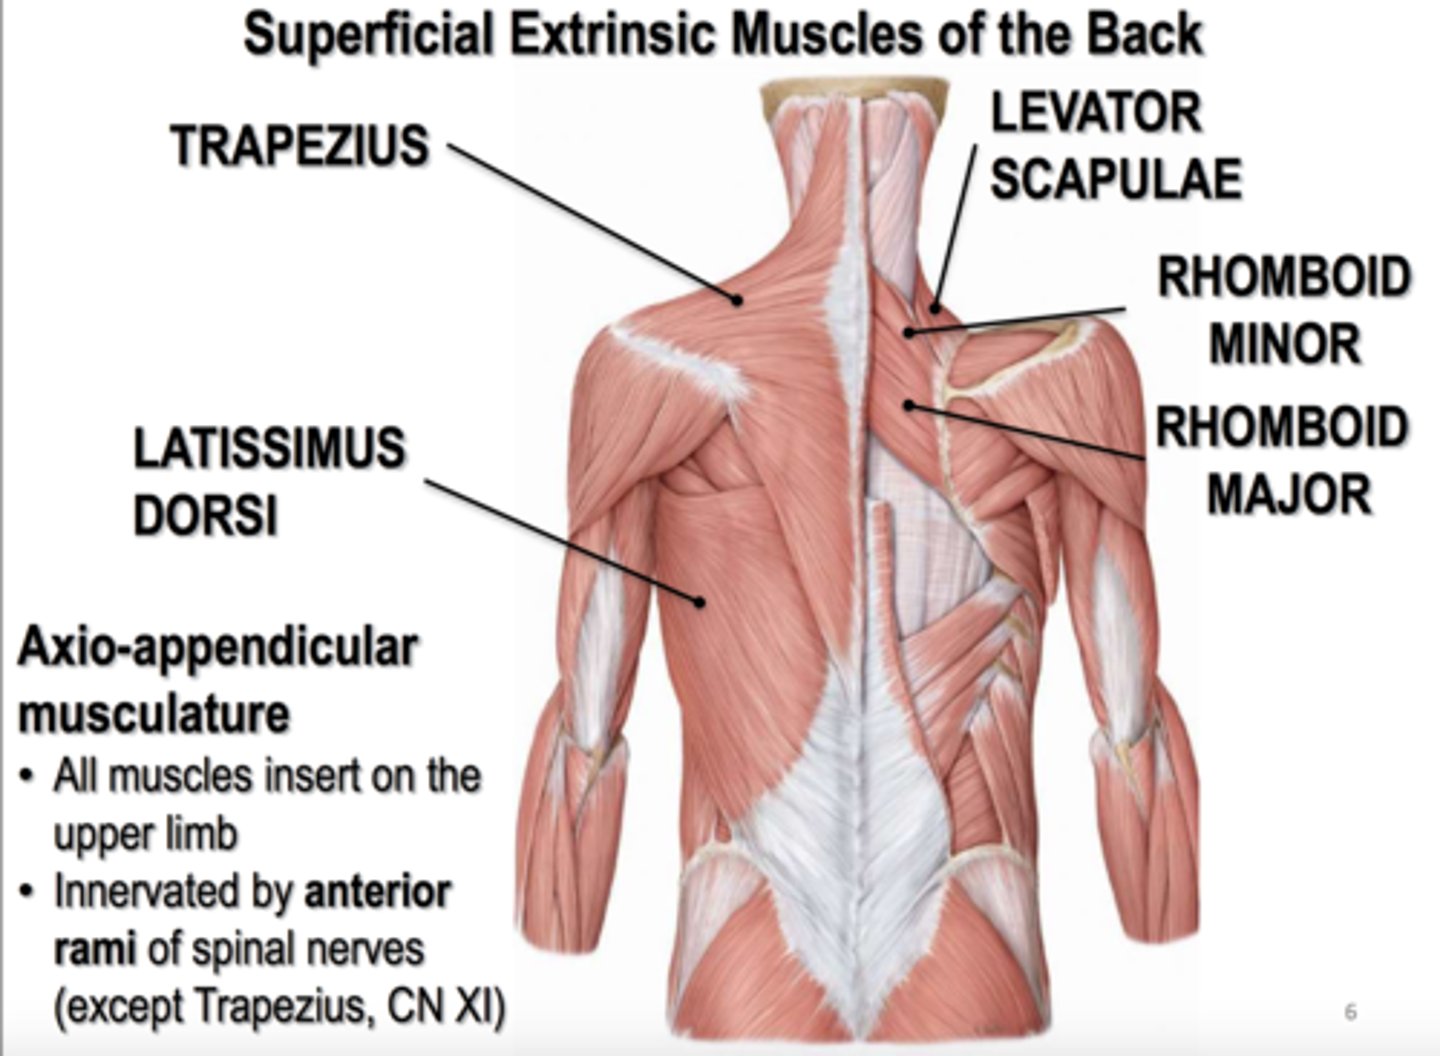

(Muscles of Pectoral region:) Posterior axioappendicular and scapulohumeral muscles

-These are superficial and intermediate back muscles and can be divided into:

*Superficial posterior axioappendicular muscles (extrinsic shoulder)

(Posterior axioappendicular and scapulohumeral muscles:) Superficial posterior axioappendicular muscles (extrinsic shoulder)

Trapezius and Latissimus dorsi

(Superficial posterior axioappendicular muscles (extrinsic shoulder):) Trapezius

-Elevates, depresses, and retracts scapula

-Accessory nerve (CN XI)

(Superficial posterior axioappendicular muscles (extrinsic shoulder):) Latissimus dorsi

-Extends, adducts, and medially rotates humerus

-Thoracodorsal n. (C6 - C8)

(Posterior axioappendicular and scapulohumeral muscles:) Deep posterior axioappendicular muscles (extrinsic shoulder)

Levator Scapulae and Rhomboid minor and major

(Deep posterior axioappendicular muscles (extrinsic shoulder):) Levator Scapulae

-Elevates and rotates scapula

-Dorsal scapular n. (C5)

(Deep posterior axioappendicular muscles (extrinsic shoulder):) Rhomboid Minor and Major

-Retract and rotates scapula

-Dorsal scapular n. (C5)